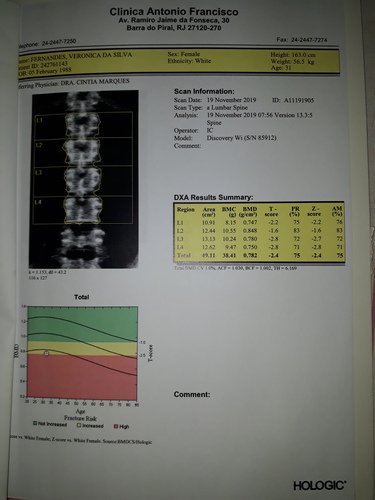

Osteoporose